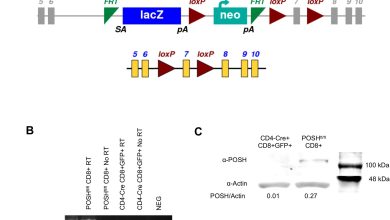

Proteína crucial permite a memória do sistema imunológico

Confirmação da exclusão do POSH no POSHfl/fl Camundongos CD4-Cre. (UM) Esquema representando o SH3rf1 originaltm1a(EUCOMM)Hmgu construção genética (parte superior) e…

Ler Mais » - Notícias